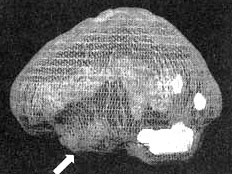

Трехмерное изображение — активный мозг, вид сбоку.